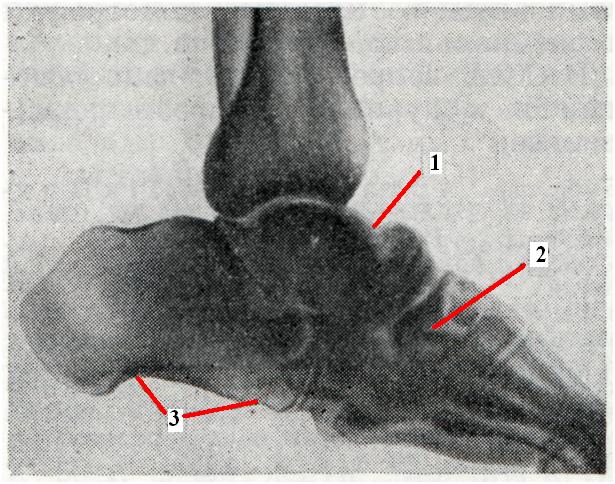

При спинной сухотке артропатия (табетическая) отмечается у 5— 10% больных. Чаще обнаруживаются изменения в коленном суставе (рис. 2), реже — в тазо-бедренном, голено-стопном, суставах позвоночника и других.

Возможны две формы табетической артропатии. При одной наблюдается внутрисуставной серозный выпот, при другой форме присоединяется деструкция суставных хрящей и эпифизов сочлененных костей. Возможно наличие отломков костей или хряща, свободно лежащих в суставе.

Пораженный сустав деформирован и нередко отечен. Однако движения в нем обычно не ограничены и безболезненны. Атрофия окружающих сустав мышц и слабость связочного аппарата приводят к разболтанности сустава.

Рис. 2. | ||

Рентгенодиагностика. Для артропатии типичны следующие основные рентгенологические признаки: рассасывание суставных концов костей (остеолиз), обезображивание их в связи с распадом костной ткани и бесформенными периостальными костными разрастаниями, остеосклероз, внутрисуставные и внесуставные патологические переломы и зоны перестройки в костях, беспорядочно расположенные параартикулярные окостенения и обызвествления, патологические вывихи и подвывихи. Своеобразной чертой артропатии является несоответствие между относительно мало нарушенной функцией сустава и грубыми морфологическими изменениями в нем. В связи с продолжающимся функционированием сустава суставные концы отшлифовываются, а отдельные костные отломки превращаются в суставные мыши.

Внесуставные переломы особенно часты при спинной сухотке (рис. 3), а лоозеровские зоны перестройки (смотри Лоозера зоны) — при сирингомиелии. Оба осложнения характеризуются образованием массивной периостальной костной мозоли.

При спинной сухотке (рис. 4) и сирингомиелии (рис. 5) возникают также внесуставные изменения в костях. Рентгенологически весьма типично рассасывание ногтевых фаланг пальцев кисти, начинающееся обычно с их свободного конца. Показательна картина заострения рассасывающихся концов костной культи. При табетической артропатии развиваются плоскостопие и genu recurvatum (дугообразное искривление ноги назад).